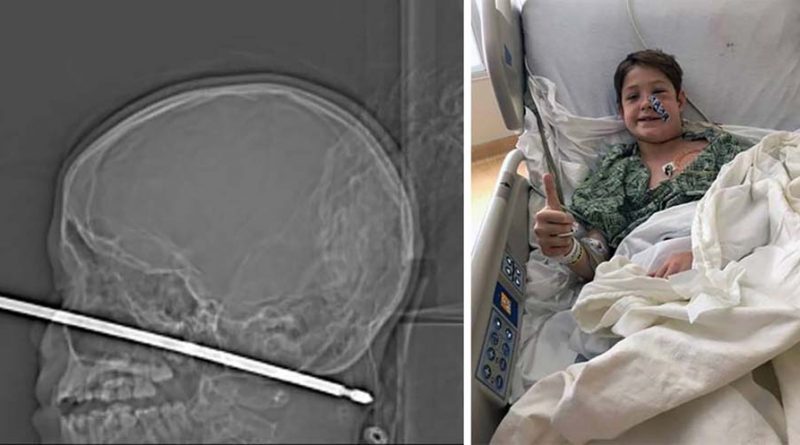

Всё произошло, когда паренёк игрался в домике на дереве, именно тогда-то на него и напали осы, которые и привели к тому, что он совершил падение с более чем метровой высоты прямо на шампур для приготовления шашлыков. Острый штырь пронзил череп мальчика, погрузившись в ткани головы на 15 сантиметров. К счастью, чудесным образом металлическая палка вошла в голову, миновав и глаза, и мозг, и спинной мозг, и крупные кровеносные сосуды.

Врачи успешно удалили квадратный стержень, так как из раны не было активного кровотечения и шампур не повредил жизненно важные органы. Сама операция была довольно непростой, в основном из-за формы шампура, который имел острые края, поэтому врачам пришлось провозиться с извлечением предмета несколько часов.

Директор отделения эндоваскулярной нейрохирургии больницы Университета Канзаса Коджи Эберсоул (Koji Ebersole) сказал, что самую большую сложность для хирургов при удалении шампура представляли кровеносные сосуды на шее паренька. Врач назвал чудом то, чтобы при такой сквозной травме шампур не повредил ничего в голове потерпевшего роковым образом.